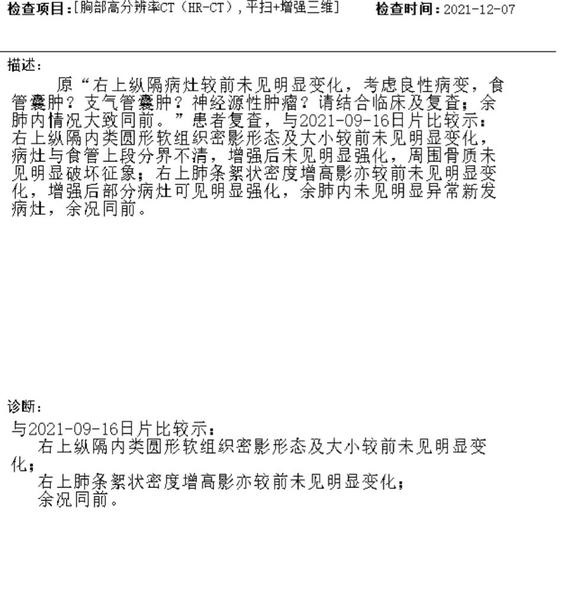

北港永下 02021-12-21 患者家属我父亲体检时发现有肿块。到人民医院检查结果显示食管囊肿或支气管囊肿本来医生说不是很大的手术。几天前做了增强ct。又说有可...